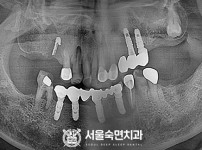

임플란트-전후사진1

임플란트-전후사진2

임플란트-전후사진3

임플란트-전후사진4

치과를-선택할-때-꼭-확인하세요-서울숙면치과-임플란트-전후사진